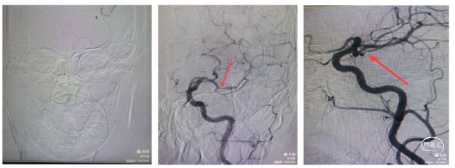

1、行右侧股动脉穿刺并置入8F动脉鞘成功。造影发现左侧大脑中动脉M3段以

远显影欠佳。正位不清晰,斜位清晰可见M3闭塞。

2、5F 125cm 中间导管抽吸:

泥鳅导丝引导8F导引导管至左侧颈内动脉C1远端平直处建立通路,微导丝引导微导管及5F 125cm 中间导管到达左侧大脑中动脉M3闭塞段近端。

近端使用60mL注射器手动抽吸两次,未见血栓取出。可能为导管未能接触血栓。

3、换用3MAX 抽吸导管通路组合:

8F MPA+3MAX抽吸导管+微导丝,抽吸两次后栓子逃逸至远端分叉部。

5、 再次跟进3MAX抽吸一次,完全再通。

术后即刻复查XperCT未见出血。